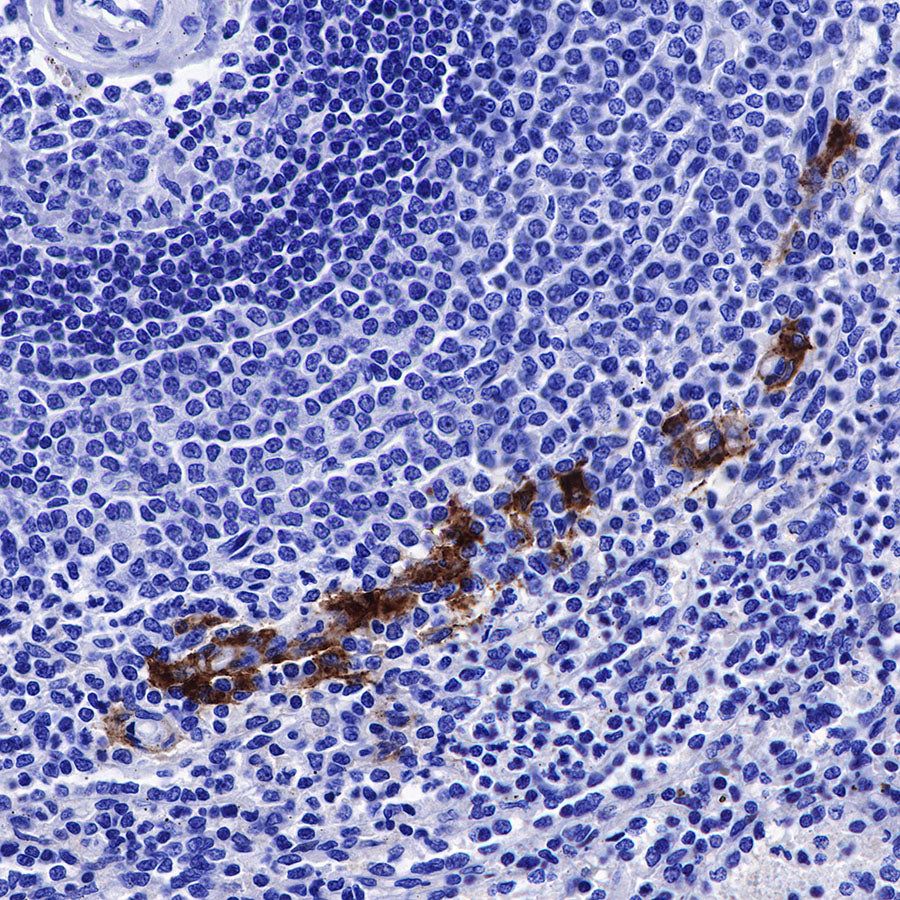

IHC shows positive staining in paraffin-embedded human spleen. Anti-CD169 antibody was used at 1/250 dilution, followed by a HRP Polymer for Mouse & Rabbit IgG (ready to use). Counterstained with hematoxylin. Heat mediated antigen retrieval with Tris/EDTA buffer pH9.0 was performed before commencing with IHC staining protocol.

Immunohistochemistry